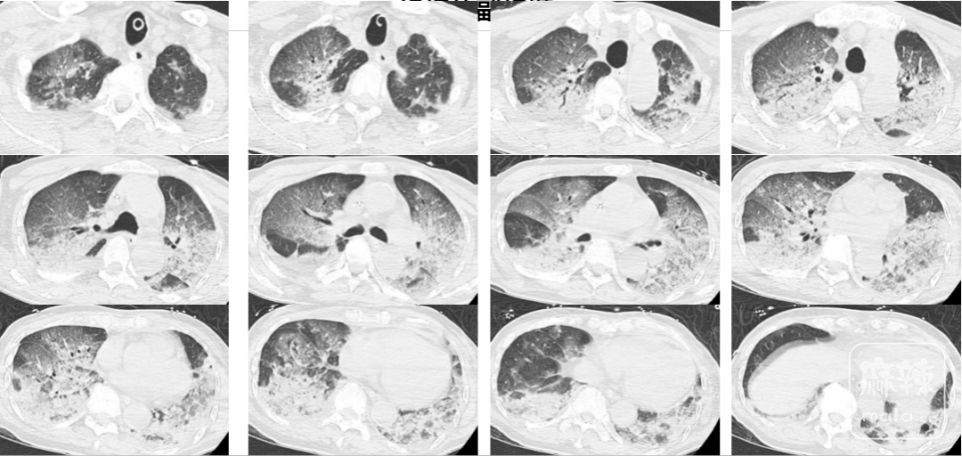

2024年12月,浙江杭州,酷爱蒸桑拿的韩爷爷(化名)于午饭后前往洗浴中心。不料刚进去没多久,整个人就昏了过去并口吐白沫,周围人帮忙拨打了120,将他送入医院。

入院时,韩爷爷意识不清,血压、心率下降,医生随即为他安排头颅、胸部CT和肺血管CTA检查,结果显示,老人的双肺出现大面积白色影像。经会诊,韩爷爷被确诊为热射病诱发的肺水肿。